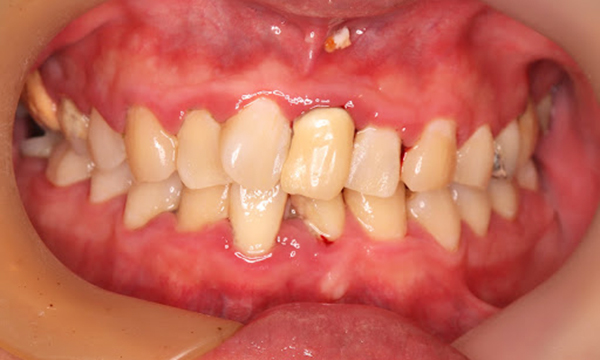

Before

症例

after

基本情報

年齢・性別 52歳・男性

主訴 主訴:久しぶりの歯医者なので歯石をとってほしい

治療部位:全顎

治療内容 1.歯磨き指導、歯肉縁上の歯石除去

2.歯磨きの確認、指導(磨けるようになるまで)

3.歯磨きの確認、指導、歯肉縁下の歯石除去(SRP)

4.PMTC

5.再評価、歯磨きの確認、指導

治療期間 1日

治療費 合計17,560円

・内訳

1、歯周基本検査・歯磨き指導、縁上スケーリング:1,800円

2、歯周精密検査・SRP(スケーリング・ルートプレーニング)、歯磨き指導:2,130円

3、SRP、歯磨き指導:3回(1,530円×3回)

4、PMTC、全顎再スケーリング、歯磨き指導:5,500円(自費診療)+1,260円

5、再評価(歯周精密検査)、歯磨き指導:2,280円

※PMTC以外、保険診療3割負担

(2023年5月現在現在)

リスク・副作用 ・毎日の歯磨きが不十分だと歯石を除去しても再度歯石がついてしまう

・最初は歯磨きのときに出血してくることがあるが、細菌が減って歯茎が引き締まってくると徐々に出血は落ち着いてくるため痛みがなければ辛抱強く磨いてもらう

・歯周病は時間をかけて静かに進行する病気なので、歯周病を治すにはそれなりに期間がかかる、すぐには治らない

・歯ぐきが引き締まると歯茎が下がり歯間に隙間ができる可能性がある

治療方針 一時的な治癒ではなく、将来的にこの治療が活かされるよう、患者さん自身である程度自己管理ができるようになることを目標とした

特記事項 ふつうのブラシと電動歯ブラシ使用(ブラウン丸型使)

歯間ブラシを1日1回は最低でも使って頂いた

担当者所見 あまり器用な方ではなかったため、決まったところがいつも磨けず奥歯に歯間ブラシがなかなか入れられませんでしたが、歯間ブラシのサイズを変えてみたり、内側から入れてみたりと試行錯誤してなんとかある程度磨けるようになりました。

その結果、出血が100%から7%へ激減することができました。

ただSRPをしただけではここまでの結果は出なかったと思います。

それほど日々のセルフケアが重要だということを再認識しました。

歯周ポケットが残っている部位、出血がある部位に関しては引き続き歯磨きを念入りに行なってもらう。